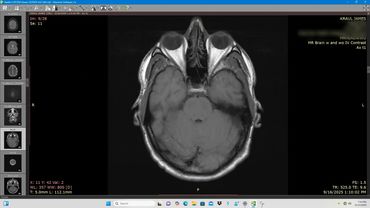

Axial MRI scan showing detailed brain structures including eye sockets and brain tissue.